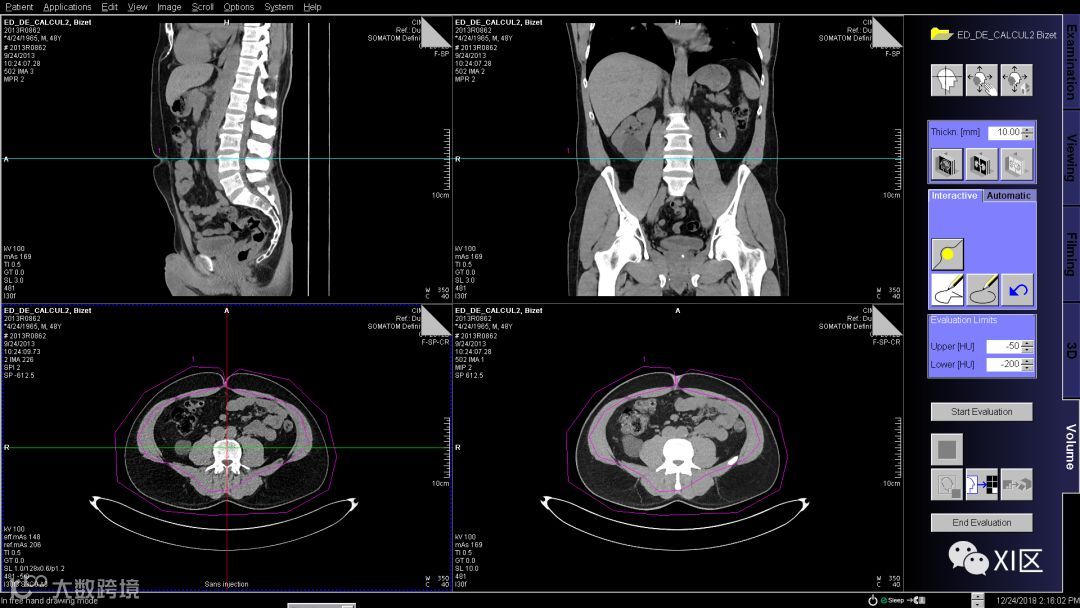

勾勒完成后如下图,修改评估阈值为-50到-200HU,然后单击开始评估获得结果。

再使用自由ROI工具将腹腔内的脂肪勾勒出来,点击开始评估,在右下像格即可获得腹壁和腹腔内脂肪的体积数据。